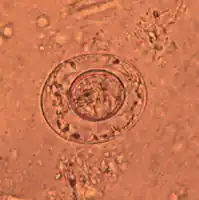

Image reveals ultrastructural details of a single Hymenolepis nana tapeworm ovum -

An egg of dwarf tapeworm

As its name implies (Ancient Greek: νᾶνος, nānos – dwarf), it is a small species, seldom exceeding 40 mm long and 1 mm wide. The scolex bears a retractable rostellum armed with a single circle of 20 to 30 hooks. The scolex also has four suckers, or a tetrad. The neck is long and slender, and the segments are wider than long. Genital pores are unilateral, and each mature segment contains three testes. After apolysis, gravid segments disintegrate, releasing eggs, which measure 30 to 47 µm in diameter. The oncosphere is covered with a thin, hyaline, outer membrane and an inner, thick membrane with polar thickenings that bear several filaments. The heavy embryophores that give taeniid eggs their characteristic striated appearance are lacking in this and the other families of tapeworms infecting humans. The rostellum remains invaginated in the apex of the organ. Rostellar hooklets are shaped like tuning forks. The neck is long and slender, the region of growth. The strobila starts with short, narrow proglottids, followed with mature ones.